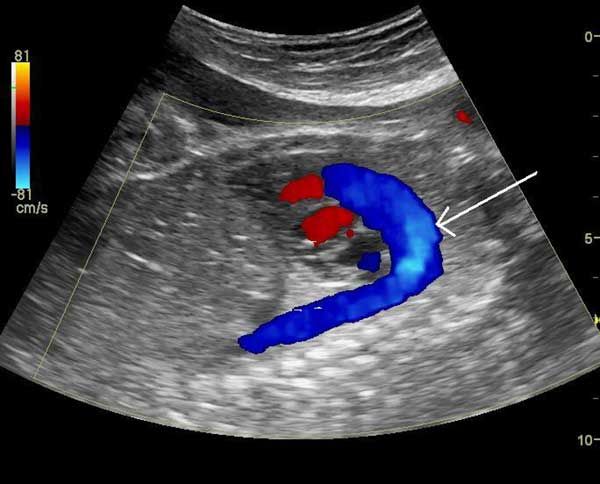

A head-to-head comparison of salpingotomy and salpingectomy finds that removing the affected tube after an ectopic pregnancy doesn’t affect fertility as expected.